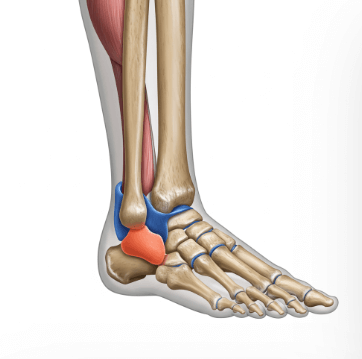

복숭아뼈는 발목 안쪽과 바깥쪽에 튀어나온 뼈로, 정식 명칭은 '복사뼈'입니다.

이 부위에 통증이 생기는 가장 흔한 원인은 발목 염좌예요. 발을 헛디뎌 인대가 늘어나거나 찢어지면서 복숭아뼈 주변에 통증과 부기가 생깁니다.

▫️ 발목 염좌 - 발을 접질려 인대 손상

▫️ 골절 및 타박상 - 직접적인 충격으로 인한 손상

▫️ 관절염 - 퇴행성 변화나 류머티즘 관절염

▫️ 힘줄 염증 - 과도한 사용으로 인한 건염

▫️ 신경 압박 - 족근관 증후군 등